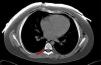

La radiografía de tórax demostró enfisema subcutáneo y neumomediastino (fig. 1). Al completar el estudio con TAC torácica para descartar alteraciones parenquimatosas, se detectó aire en el canal raquídeo limitado al espacio epidural (fig. 2).